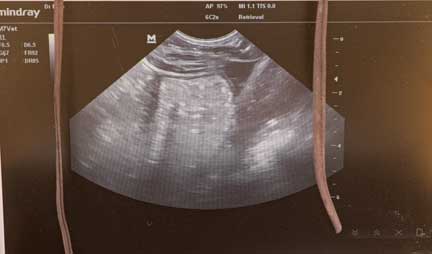

Checking this female with ultrasound for pregnancy

Affirmative on that pregnancy!